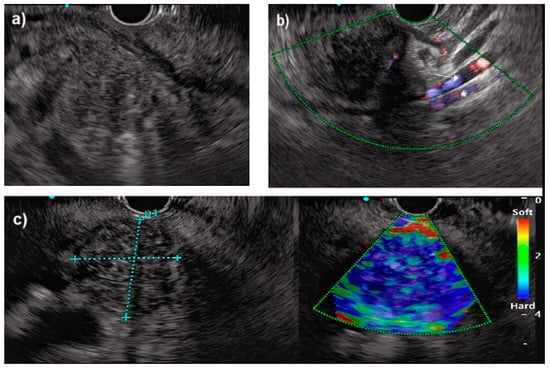

3.2. Endoscopic Ultrasound